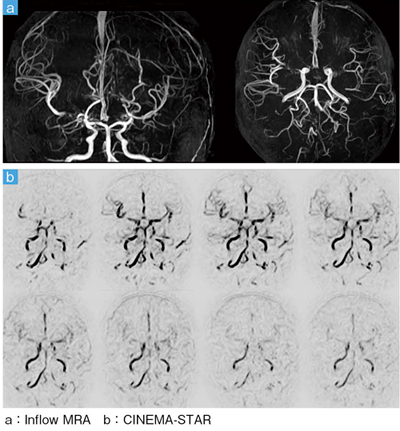

■症例1:もやもや病(6歳,男児)の頭部MRA